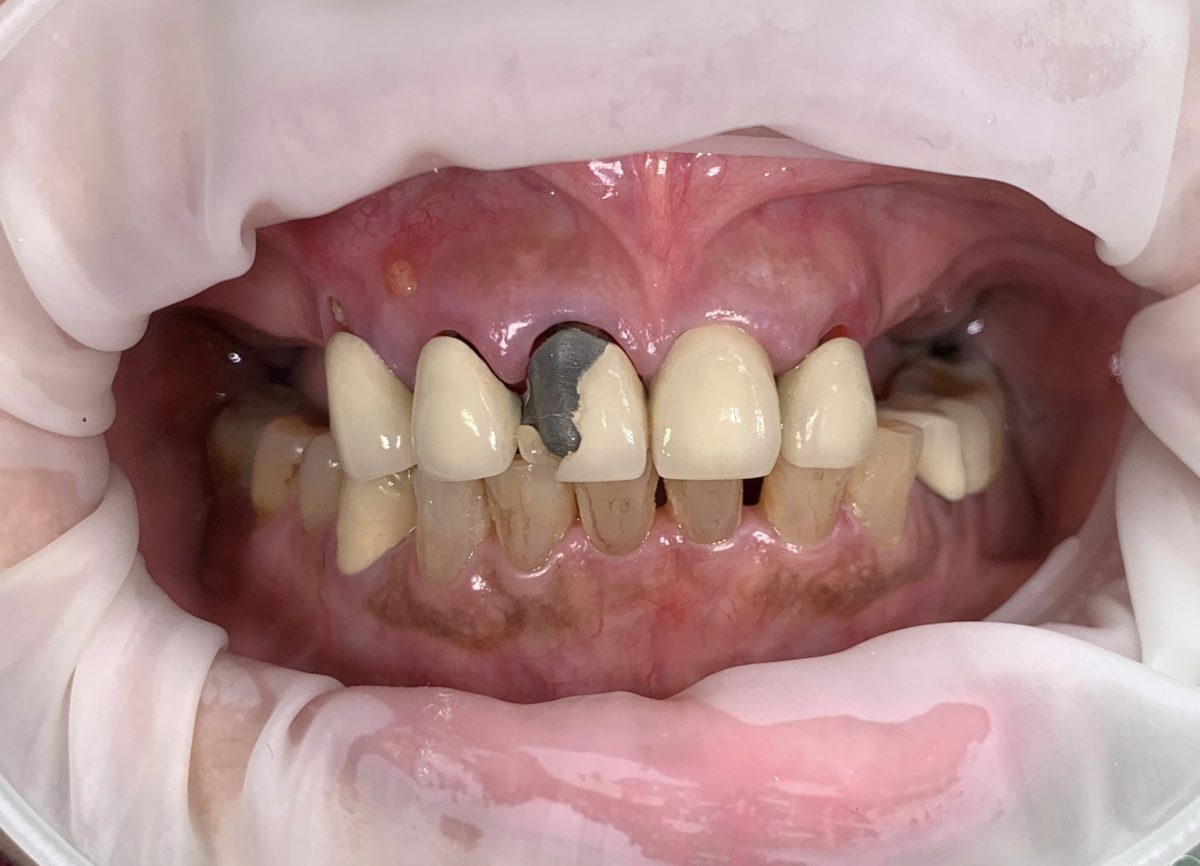

All-on-X dental implants are a full-arch restoration solution designed for patients with multiple missing, damaged, or failing teeth. The treatment uses four, five, or six dental implants to support a fixed full-arch prosthesis, restoring both function and aesthetics.

Full mouth rehabilitation is a comprehensive dental treatment designed to restore both function and aesthetics for patients with severely worn, damaged, missing, or failing teeth.

Treatment may include a combination of:

* crowns

* veneers

* dental implants

* bridges

* gum treatment

* bite rehabilitation

Each treatment plan is customized based on the patient’s oral condition and long-term goals.

Yes. We provide personalized smile makeover consultations based on your facial profile, dental condition, bite, and aesthetic goals.

Our dentists focus on creating natural-looking smiles that balance aesthetics, comfort, and long-term function.